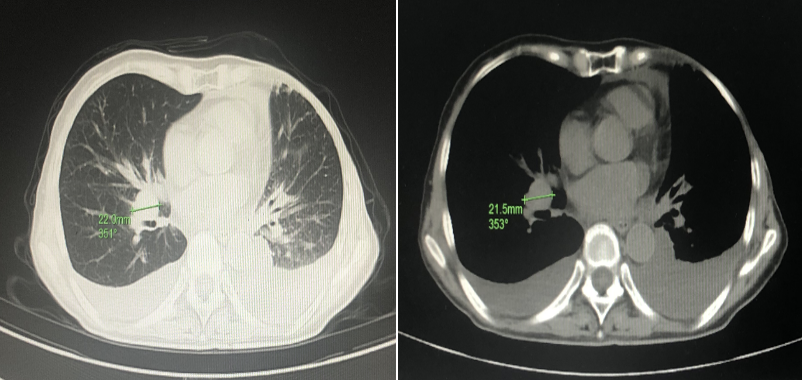

患者于2021年7月常规门诊复查。

双锁骨上淋巴结超声:双侧锁骨上低回声结节,考虑异常肿大淋巴结。

胸部CT:纵隔及右肺门多发淋巴结,部分肿大,较前新增,双侧胸腔积液

伴双肺局部膨胀不全,较前进展。

无病生存期(DFS):近12月。

晚期一线方案:T-DM1(体重:37kg,130mg,3.6mg/㎡,1/21d)(依据CSCO BC指南 EMILIA研究结果)。